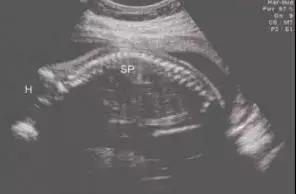

宝宝在妈妈的肚子里时候一直是蜷缩状,整个脊柱是一条向后弯的 C 型。

图片来源:张珏华,朱世亮主编. 妇科与产科超声图谱. 2008.

宝宝出生后,脊柱还是 C 型的,平躺时脊椎和颈椎就是一个平面,这时非要硬塞一个枕头进去,不但不舒服,还会阻隔宝宝顺畅的呼吸。